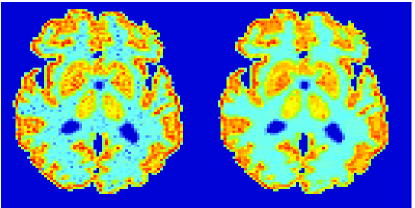

In the images shown in the figures we illustrate the calculated uptake rates of the FDG. Images for the CMRGlc can be obtained by directly scaling . In figure 1 we compare the result of using Patlak and TV-Patlak for estimating the uptake rates with respect to no noise, noise in the input function, Poisson noise in the sinogram, and finally with respect to the case in which the irreversibility assumption is violated but without noise in the sinogram or input data. In each case the histogram of the relative errors is given on the left, the Patlak image in the middle and the TV-Patlak on the right. The different scales in the histograms are due to the total number of results illustrated. When there is no noise (triples and ) the histogram illustrates results over all voxels but only one simulation, while for the noisy simulations the results are for all voxels over all realizations of the noise. The TV-Patlak images are more homogeneous in all cases and the relative errors are smaller. The figures clearly show the improvements of employing the TV-Patlak method as compared to using Patlak independently for each voxel. This is confirmed in figure 2 in which images with noise in the sinogram, positive and different noise levels in the input function are shown.